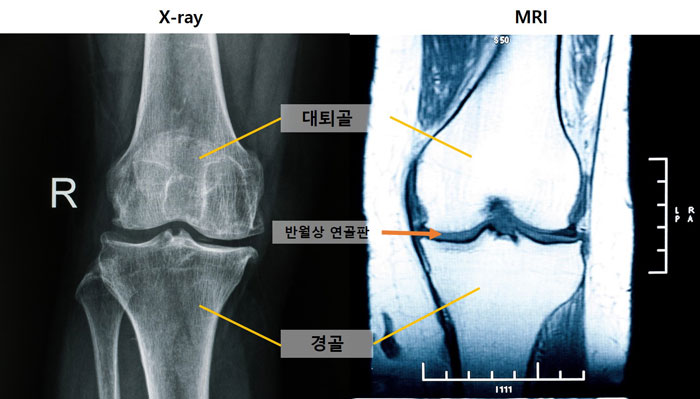

[병원뉴스]무릎 관절염 조기 진단하는 새로운 MRI 지표 확인

무릎 관절염 조기 진단하는 새로운 MRI 지표 확인 - 국내 연구팀, 무릎 관절염 환자 1140명의 MRI 및 X-ray 데이터 연관성 분석 - MRI서만 확인되는 중앙 대퇴골 연골 손상, 무릎 관절염 초기 단계의 핵심 변화 [사진 왼쪽부터] 엑스레이 및 MRI 무릎 사진 무릎 관절염을 조기에 발견할 수 있는 새로운 진단 지표가 확인됐다. 엑스레이에서 정상으로 진단된 무릎이라도, MRI에서 중앙 대퇴골 연골 손상 소견이 관찰된다면 무릎 관절염이 이미 진행되고 있을 가능성이 높다는 사실을 국내 연구팀이 규명했다. 또한 MRI로 내측 반월상 연골 돌출이 관찰되면 관절염이 심각해질 위험이 높은 것으로 나타났다. 서울대병원 정형외과 노두현한혁수 교수, 동국대일산병원 이도원 교수팀이 미국 장기 관절염 코호트(MOST)에 등록된 50세 이상 무릎 관절염 환자 1140명의 데이터를 기반으로, MRI 및 엑스레이 소견을 장기 추적한 결과를 23일 발표했다. 무릎 퇴행성관절염은 연골의 점진적인 손상과 관절 구조물의 퇴행성 변화로 인해 발생하는 질환으로, 전 세계 인구 10명 중 1~3명이 앓고 있다. 이 질환은 통증과 운동 제한을 유발해 삶의 질을 크게 낮출 수 있어, 조기 진단과 치료를 통해 진행을 늦추는 것이 중요하다. 무릎 관절염 초기에는 연부조직(연골, 반월상 연골판 등)에서 먼저 변화가 발생하지만, 일반적으로 진단에 활용되는 엑스레이로는 이런 변화를 일찍 파악하는 데 한계가 있다. 연부조직을 관찰하기 용이한 MRI는 접근성이 떨어지며, 이처럼 서로 다른 특성을 가진 두 검사 방법의 연관성을 장기적으로 분석한 연구는 드물었다. 연구팀은 엑스레이로 평가한 관절염 진행 단계(0~4기)에 따른 주요 MRI 소견을 최대 7년간 추적 관찰했다. 그 결과, 관절염 진행 시 가장 먼저 나타나는 변화는 중앙 대퇴골 연골 손상이었다. 이 손상은 엑스레이에서 정상으로 여겨지는 관절염 0기부터 관찰되어, MRI가 무릎 관절염 초기 변화를 확인하는 데 중요한 도구임을 보여줬다. 표 [그래프] 무릎 관절염 진행 단계에 따른 MRI 소견. 관절염 0기(빨간 선)에서도 중앙 대퇴골 연골 손상이 관찰돼, 이 손상이 무릎 관절염의 중요한 초기 증상으로 나타났다. 또한, 관절염 진행 위험의 가장 강력한 예측 인자는 반월상 연골 탈출이었다. 추적 관찰 시간은 유의미한 연관성이 없어, 시간 경과보다는 무릎의 구조적 변화가 관절염 진행을 주로 유도하는 것으로 확인됐다. 한편, 관절염 진행에 따라 MRI상 무릎 중앙에서는 연골반월상 연골판뼈, 후방에서는 반월상 연골판연골뼈 순서로 손상 양상에 차이가 있었다. 추가적으로 연구팀은 관절염 초기 MRI 소견(중앙 대퇴골 연골 손상)과 연관된 엑스레이 지표를 분석했다. 그 결과, 경골 골극, 내측 관절강 협착, 대퇴골 골극 순서로 엑스레이 소견이 나타났고, 이들은 모두 연골 손상과 연관성이 있었다. 서울대병원 노두현 교수(정형외과)는 이번 연구를 통해 무릎 관절염의 구조적 변화 순서를 체계적으로 규명하고, 조기 관절염을 예측하는 핵심 인자를 입증했다며 또한 MRI 이용이 제한된 환경에서는 특정 엑스레이 소견을 이용해 관절염의 발생과 진행을 간접적으로 예측하고, 일찍부터 관절염 진단의 효율성을 높일 수 있을 것으로 기대된다고 말했다.한편, 이번 연구 결과는 2025년 대한슬관절학회 국제학술대회(ICKKS 2025)에서 우수 발표상을 수상했으며, 국제학술지 Knee Surgery Sports Traumatology Arthroscopy 최신호에 게재됐다. [사진 왼쪽부터] 서울대병원 정형외과 노두현 교수, 동국대일산병원 정형외과 이도원 교수